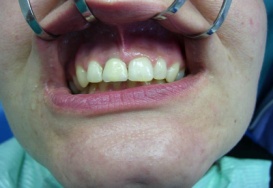

Bezzubá čelist je hlavní indikací pro ošetření pomocí implantátů. Zejména celkové zubní náhrady v dolní čelisti mají velice nízkou stabilitu a držení díky velkému úbytku kosti.

S pomocí zubních implantátů můžeme díky různým kotevním systémům (třmeny, kulové hlavy, Locatory) zajistit stabilitu a držení protézy nebo při použití většího počtu implantátů zhotovit pevné náhrady – můstky nalepené nebo našroubované na pevno na implantáty.

S těmito typy náhrad můžeme dosáhnout perfektní funkci, výbornou estetiku, fonetiku a současně zajistit u pacienta možnost dobré hygienickou péče a čištění, která je pro životnost implantátů velice důležitá.